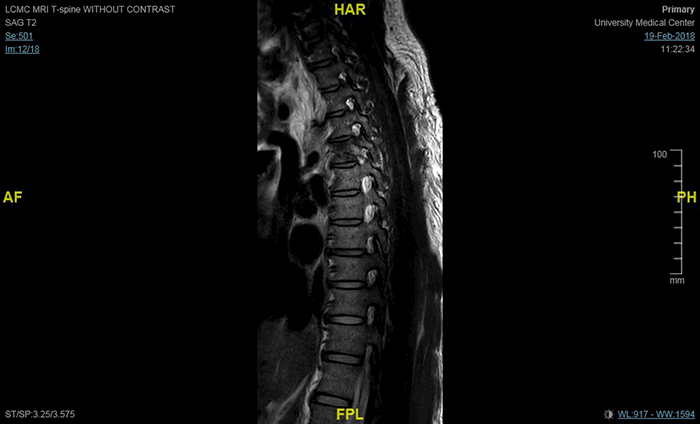

On postoperative day 1, the patient underwent a re-exploration of the right thoracic cavity, with removal of the packs and wound closure. No further evidence of bleeding was observed intra-operatively. A post-operative CT scan showed a T5 vertebral body fracture and T6 superior articular facet fracture (Figure 5). MRI demonstrated partial transection and contusion at T5 (Figure 6). The patient remained in the ICU for 9 days post-operatively. He had continued bilateral lower extremity paralysis below level T4. He was subsequently discharged to inpatient neurologic rehabilitation on post-operative day 11. At the time of discharge, the patient had permanent paraplegia below T3. The patient was seen in clinic seven months after his injury with no further neurologic recovery.

Figure 6. MRI thoracic spine without contrast, T2: sagittal view